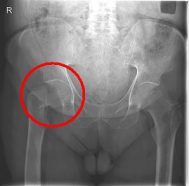

In addition to a thorough physical examination, radiographs of the pelvis and the affected hip are crucial for the diagnosis.

Images: Here is the supply of a dynamic hip screw shown.

In younger patients and a minor shift, the goal is to preserve the femoral head. The blood supply to the femoral head is at risk for medial femoral neck fractures, so that the fastest possible care should be sought if one wants to preserve the femoral head. Among others, the dynamic hip screw (DHS) is available for this purpose.